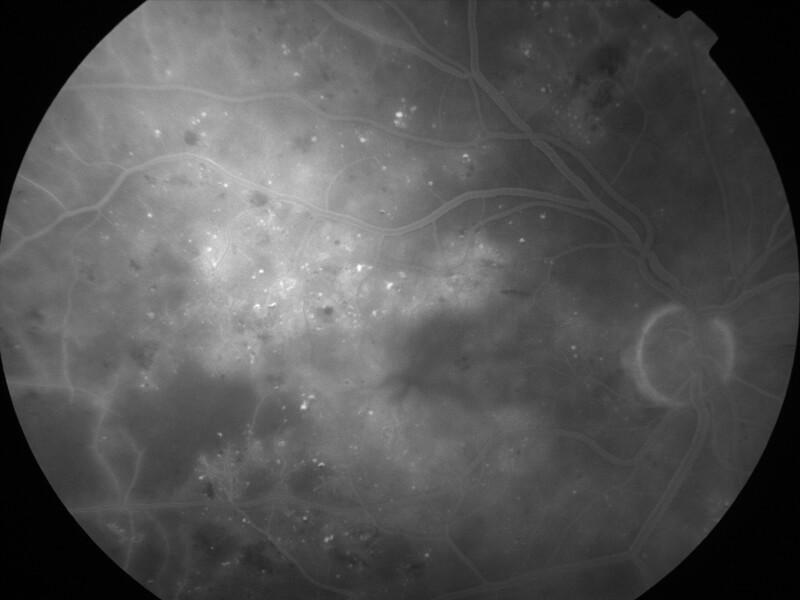

rétinopathie diabétique pré-proliférante

IM000021.jpg